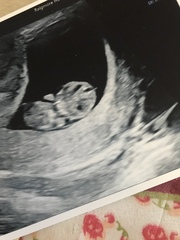

Back from my scan, bub measured 9+3 which is exactly what we thought. Heartbeat, two arms and two legs kicking 😊 it was so amazing to see bub wriggling and moving around, I’m just so in love. Also got my letter from hospital today and my 12 week scan is 24th July 😬

Forgot to attach photos!

Awww lovely photos @hayleyfx. I know what you mean-so easy to fall in love with that little black and white wiggler.

@hayleyfx gorgeous scan pics!

@hayleyfx Lovely photos! Thanks for sharing 😊

Beautiful photos @hayleyfx congrats! It's such a wonderful feeling isn't it. I loved my 9 week scan but now at 11 weeks I'm all worried and panicky again! 😂 don't think I'll rest until I have my bub in my arms! X

@hayleyfx So lovely, and how amazing that baby was moving, I can't wait to see that 😍

Congrats on scans @hayleyfx and @clairehr amazing pics.